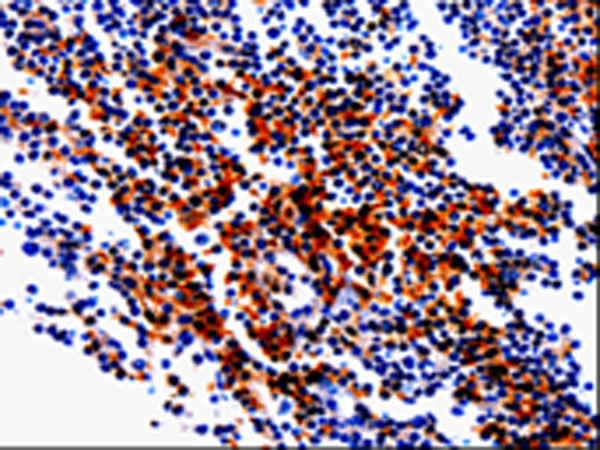

分类: 科研抗体货号: P06987别名: BBC2; BCL2L8应用: IHC反应种属: Human